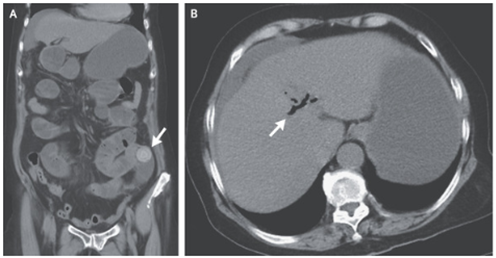

結腸原発と考えられる転移性神経内分泌腫瘍を背景にしたカルチノイド心疾患の一例

67歳男性。 約1か月前から呼吸困難、下痢が出現し、昨日から腹痛が出現したため外来を受診した。 身体所見では頚静脈怒張、左胸骨下縁の全収縮期雑音、びまん性喘鳴、…